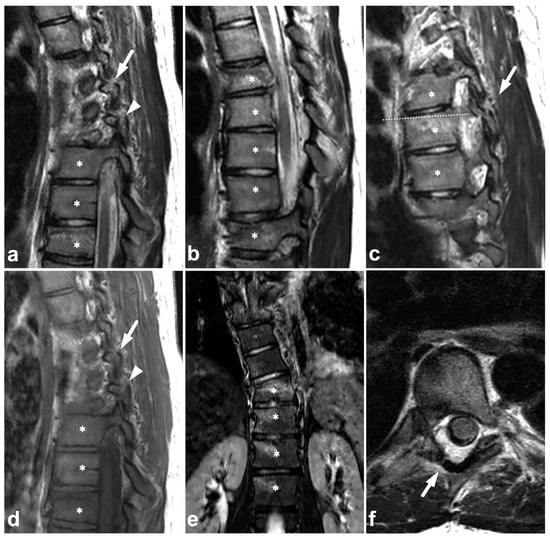

Figure 7.

(a) Sagittal left-sided off-midline T2-weighted. (b) Sagittal T2-weighted. (c) Sagittal right-sided off-midline T2-weighted. (d) Sagittal left-sided off-midline T1-weighted. (e) Coronal STIR. (f) Axial T2-weighted (dotted line on the image (c)). A 17-year-old female with a history of idiopathic juvenile scoliosis and acute spinal trauma due to a motorcycle accident. The patient had fractures and contusions in multiple vertebrae; the injuries in Th6, Th7, Th8, Th9, and Th10 (asterisks) are seen in the presented images. In addition to vertebral body fractures, the posterior elements were involved bilaterally in Th6 (arrows) and on the left side in Th7 (arrowhead). Facet joints remained congruent. Burst-like morphology is seen on the Th6 fracture. In image (b), the fracture seems to dislocate the spinal cord, but in the axial plane (not presented here), the cord was seen not to be compressed.